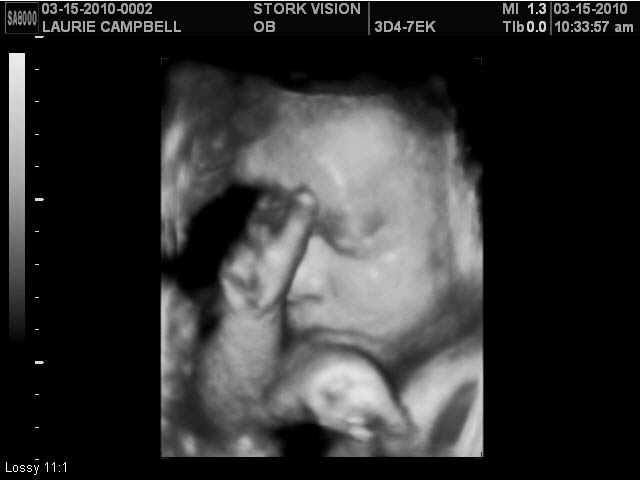

Womb with a View

Had the fantastic opportunity to See my little baby bean growing last week at 31 weeks. A friend just purchased the Fort Worth Stork Vision. I recamend this place to anyone wanting an awesome view of thier growing baby.

We all think this little one looks much like my 3rd daughter Krisalyn. Now to see if she'll have those adorable dimples too.